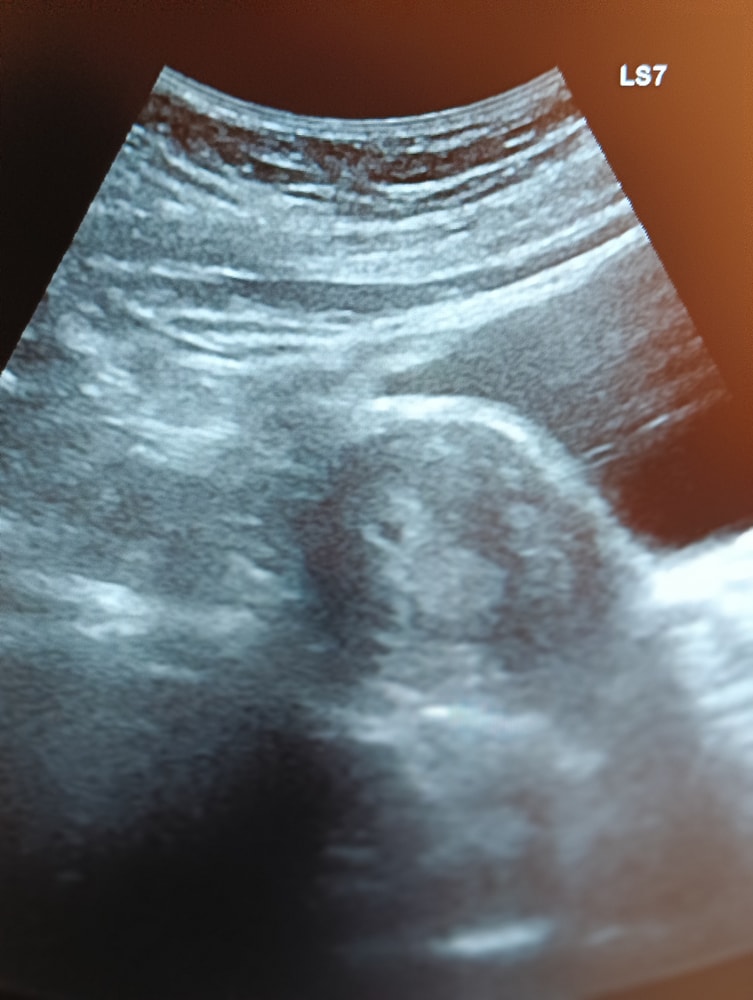

По циклу это должно было быть уже недель 5-6, а нашли вообще мизерное.

Изображение